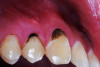

(2.) Lingual and facial maxillary views of 5-year-old patient, 1 year after caries attenuation with SDF. The parents were not concerned about the black staining.

Figure 2

(3.) Lingual and facial maxillary views of 5-year-old patient, 1 year after caries attenuation with SDF. The parents were not concerned about the black staining.

Figure 3